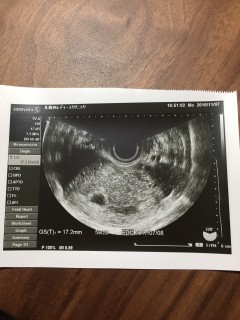

5w0dでたいのうが確認できました!とても小さくて不安でしたが、先生に「順調ですよ」と言ってもらえてほっとしました!

長い間不妊治療をしてきてようやく授かった命。 実は2ヶ月前に体外授精後、妊娠8週目で完全流産してしまい、辛かったけどここまで諦めないで頑張ってきて良かった。 つい先日、鮮血と下腹部痛に見舞われたけど止血剤と痙攣を止める薬を処方してもらい、なんとか無事。 赤ちゃん、このまま無事に元気に産まれてきてね。 4.2㎜でした。